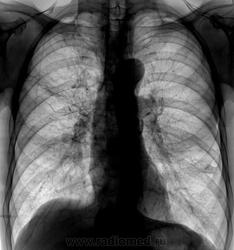

Очаги на верхушке справа, справа фиброзные изменения на уровне 3 ребра, междолевая горизонтальная плевра справа смещена вверх, видимо за счёт фиброза. Слева апикально плевральные наслоения. в проекции 4 м/р вроде бы 2 округлые очаговые тени (одна рядом с корнем)?. Очаговый ТВС верхней доли справа? Возможно гиповентияляция верхней доли справа. Хотелось бы архив

Валентин Львович! А Вы часом не в ПТД устроились работать(подрабатывать)?Патология-в верхней доле и S6 правого легкого . Точно о характере ( очаговый или инфильтративный )и наличии полостей распада правильно судить можно только п/тмг дообследования.